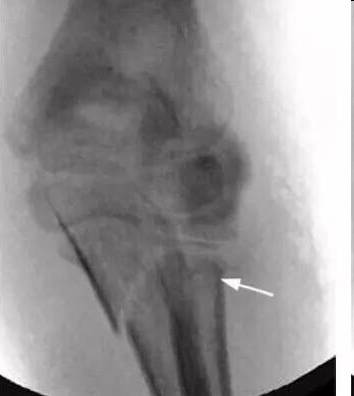

6 岁患者发生 Monteggia 骨折,肘关节造影术术中前后位透视可见经闭合复位后的桡骨颈骨折(白色箭头)和尺骨鹰嘴骨折